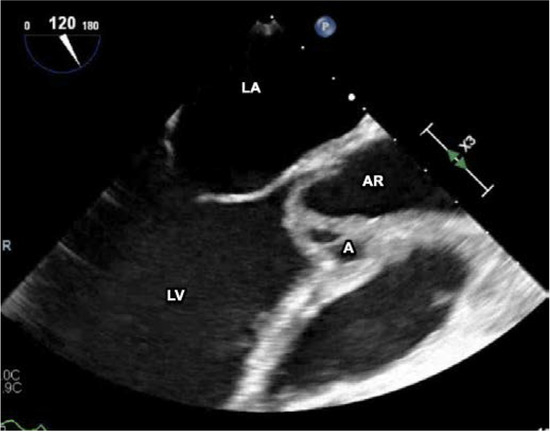

Introduction: Neisseria elongata, which is part of the normal oropharyngeal bacterial flora, can be an aggressive organism causing serious infections including infective endocarditis. N. elongata infective endocarditis is rare and no current guidelines exist to direct antibiotic selection and/or duration of treatment. Case report: We report a case of infective endocarditis due to N. elongata and a review of the literature. Our patient is a healthy young woman, who was found to have an aortic root abscess with valve perforation requiring valve replacement. Discussion: N. elongata infective endocarditis typically affects the left cardiac chambers and is associated with high risk of embolization. A transesophageal echocardiogram should be performed as part of the initial workup to assess the extent of infection, as a high percentage of patients develop perivalvular abscess formation and/or valve perforation. Most patients require prolonged antibiotic therapy and early surgical intervention. Conclusions: This case demonstrates the potential severity of N. elongata endocarditis. Further studies are needed to establish management guidance. Full article

Figure 1